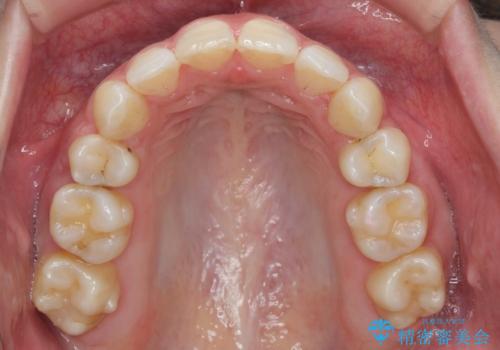

ガタつきと口元の改善 抜歯を伴うワイヤー矯正

- 唇の閉じづらさと、前歯のがたつきの改善を希望され来院されました。

抜歯を行わなくてもなんとか並べられる歯並びですが、唇の閉じづらさをしっかりと改善するため抜歯を伴うマルチブラケット矯正を行うこととしました。

前歯をしっかりと後方に引いたことで、唇は閉じやすくなり、仕上がりに満足いただくことができました。